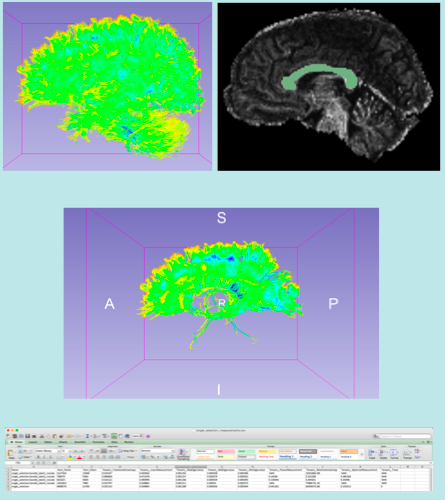

This tutorial guided you through the fiber bundle label selection and fiber tract scalar measurements to select fiber bundles passing through region(s) of interest and calculate scalar measurements (such as FA and trace) from fiber bundles.

- Image Media:FiberBundleSelectionAndScalarMeasurement_TutorialContestWinter2016_Snapshot.png